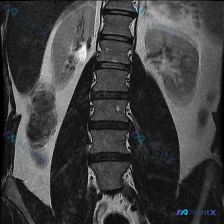

用户的初始问题很明确:“这张图里能看到什么状况?脊柱侧弯?”

但拿到的腰椎MRI T2加权冠状位影像描述里,关于脊柱形态的结论是:

腰椎序列大致连续,未见明显的侧弯或旋转畸形,椎体高度大致正常,形态规整。

反而有另一个更突出的信号学表现:

各椎间隙椎间盘(髓核)T2信号普遍不同程度降低,提示水分丢失和退行性变。

神经根走行、关节突关节、椎旁软组织在这个层面也未见明显异常。

当然,报告也特意强调了:单凭一张冠状位没法完整评估椎间盘后方突出、侧隐窝压迫的细节,必须结合矢状位、轴位综合看。

📋答案:1. 明确无脊柱侧弯:影像显示腰椎序列排列规整,未见侧弯或旋转畸形;2. 核心影像表现为多节段腰椎间盘髓核脱水退变(T2加权像低信号);3. 仅凭单张冠状位无法完整评估椎间盘后突及侧隐窝情况,需结合多方位图像;4. 需警惕预设诊断带来的确认偏误/锚定效应